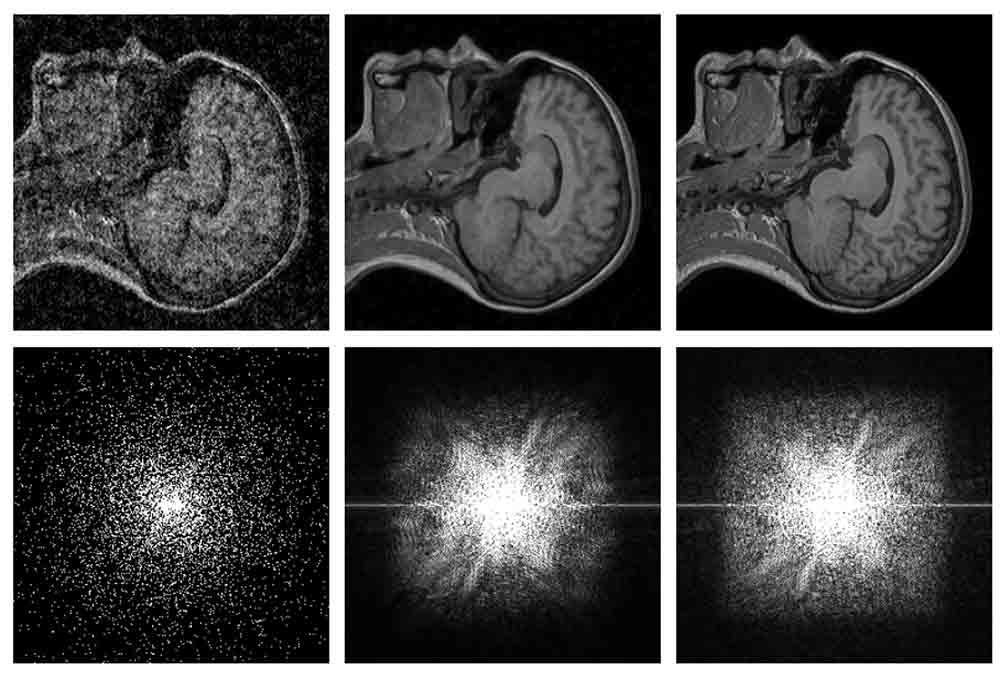

Für das Training griff das Forscherteam auf 50.000 Bilder des Imagenet zurück, einer für KI-Forschung optimierten Bilddatenbank. Die Wissenschaftler wählten an sich einwandfreie Bilder und fügten jeweils zweimal ein Bildrauschen hinzu. Die beiden auf unterschiedliche Weise verrauschten Bilder dienten dem künstlichen neuronalen Netz anschließend als Trainingsmaterial. Zum Einsatz kamen Fotografien, computergenerierte Bilder und MRT-Scans.

Das Besondere an dem "Noise2Noise" genannten KI-System: Es kann das Originalbild rekonstruieren, ohne es jemals in unbeschädigtem Zustand gesehen zu haben. Ein früheres KI-Experiment Nvidias kann unter anderem Gesichter in Fotos rekonstruieren - selbst wenn eine Vielzahl Pixel fehlen. Das künstliche neuronale Netz lernte jedoch mit Hilfe intakter Bilder. Noise2Noise leistet Ähnliches, aber (wie schon der Name nahelegt) nur anhand zweier, gleichermaßen beschädigter Bilder.

Nvidia sieht eine Reihe möglicher Anwendungsszenarien für die KI-Technologie. Von Teleskopen erstellte Langzeitaufnahmen des Nachthimmels könnten nachträglich ausgebessert werden. Die KI könnte außerdem helfen, das Bildrauschen in MRT-Scans zu reduzieren, das bisher ein recht zeitaufwendiges Verfahren ist. Mit Hilfe der KI könnten Ärzte schneller Diagnosen stellen.